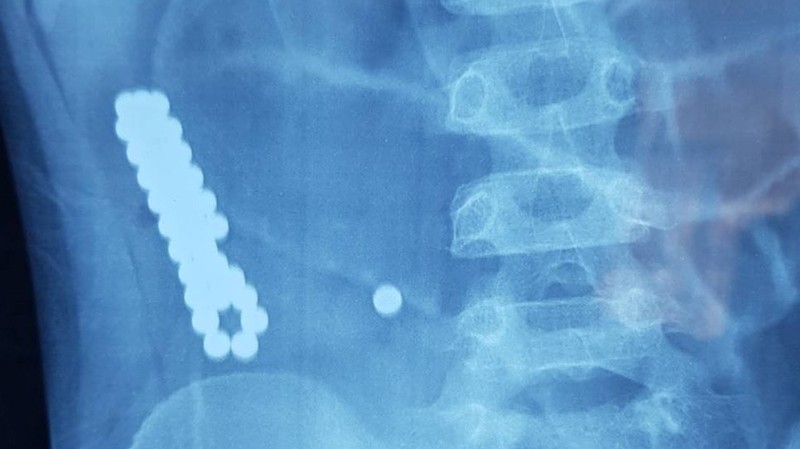

Магнитные шарики на рентгене: Интересные находки

Раздел: Картинки на заметку